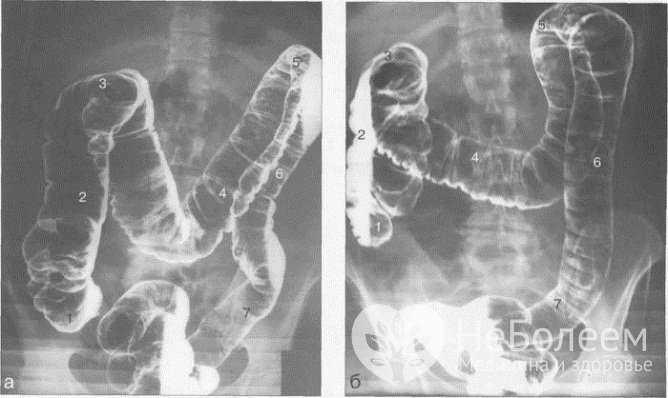

Наиболее информативным методом исследования моторной функции толстого кишечника представляется ирригоскопия – контрастная рентгенография толстой кишки после бариевой клизмы, качественно визуализирующая труднодоступные участки кишечника, недоступные для колоноскопии (складки слизистой оболочки, изгибы ободочной и сигмовидной кишки и т. д.). При подозрении на перфорацию или непроходимость толстой кишки вместо бариевой взвеси вводят водорастворимый контрастный препарат. После опорожнения кишечника проводится исследование рельефа слизистой оболочки толстой кишки. При необходимости для лучшей визуализации внутренней стенки кишечника в просвет кишки нагнетается кислород.

Ирригоскопия – наиболее информативный метод диагностики атонии кишечникаЭндоскопическое исследование толстой кишки с отбором биоптата целесообразно для дифференциальной диагностики с онкопатологией, болезнью Крона и другими заболеваниями, характеризующимися специфическими изменениями кишечного эпителия.